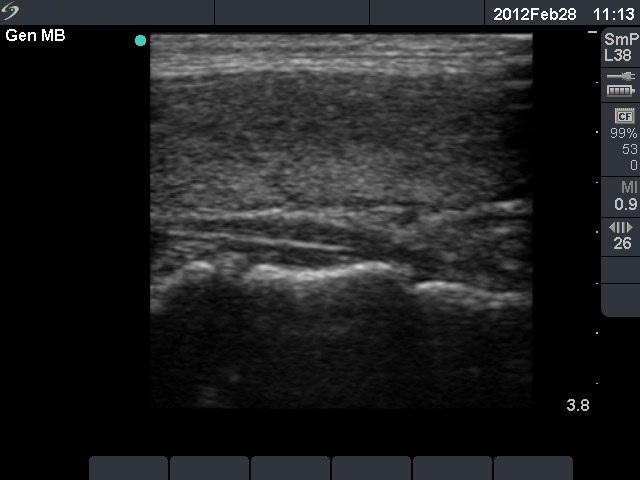

Initial investigation 5 months after delivery (1st and 2nd rows of images)

Ultrasonography: the thyroids were echonormal. The echogenicity index was around 15%. There was no nodule. The vascularization was average.Cytology resulted in Hashimoto's thyroiditis.